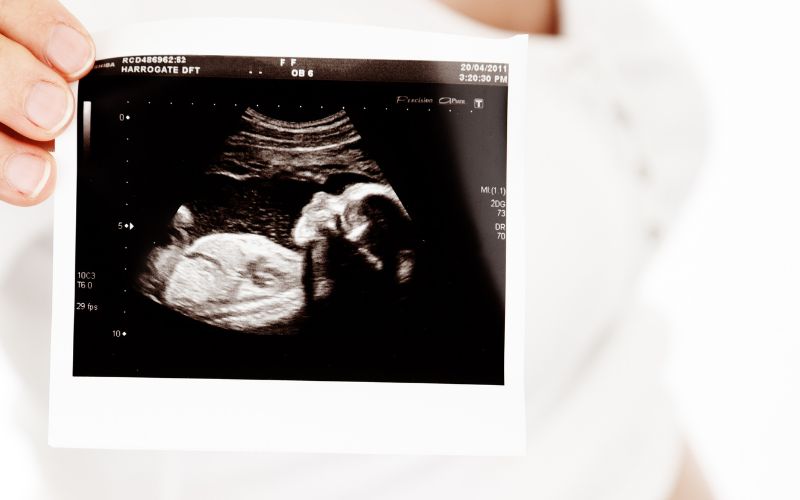

Siêu âm 3D - 4D còn được gọi là siêu âm 3 chiều - 4 chiều. Các sóng siêu âm được truyền xuống với nhiều góc độ khác nhau, hiển thị hình ảnh trên máy tính là không gian ba chiều, đối với siêu âm 4D sẽ có thêm chiều thời gian thực. Thông thường, phương pháp này được chỉ định để khảo sát cấu trúc gương mặt hoặc tim của thai nhi.